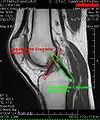

Intracapsular

The knee is stabilized by a pair of cruciate ligaments. These ligaments are both extrasynovial, intracapsular ligaments.[17] The anterior cruciate ligament (ACL) stretches from the lateral condyle of femur to the anterior intercondylar area.[13] The ACL is critically important because it prevents the tibia from being pushed too far anterior relative to the femur.[13] It is often torn during twisting or bending of the knee.[18] The posterior cruciate ligament (PCL) stretches from medial condyle of femur to the posterior intercondylar area. This ligament prevents posterior displacement of the tibia relative to the femur.[13] Injury to this ligament is uncommon but can occur as a direct result of forced trauma to the ligament.

Both anterior cruciate ligament (ACL) and posterior cruciate ligaments (PCL) are hypointense on both T1 and T2 weighted images of MRI. However, some high signal striations are often seen at the distal part of the ACL, making ACL higher intensity than PCL on MRI scans.[17]